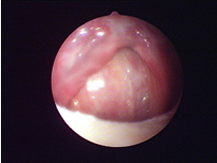

經典案例